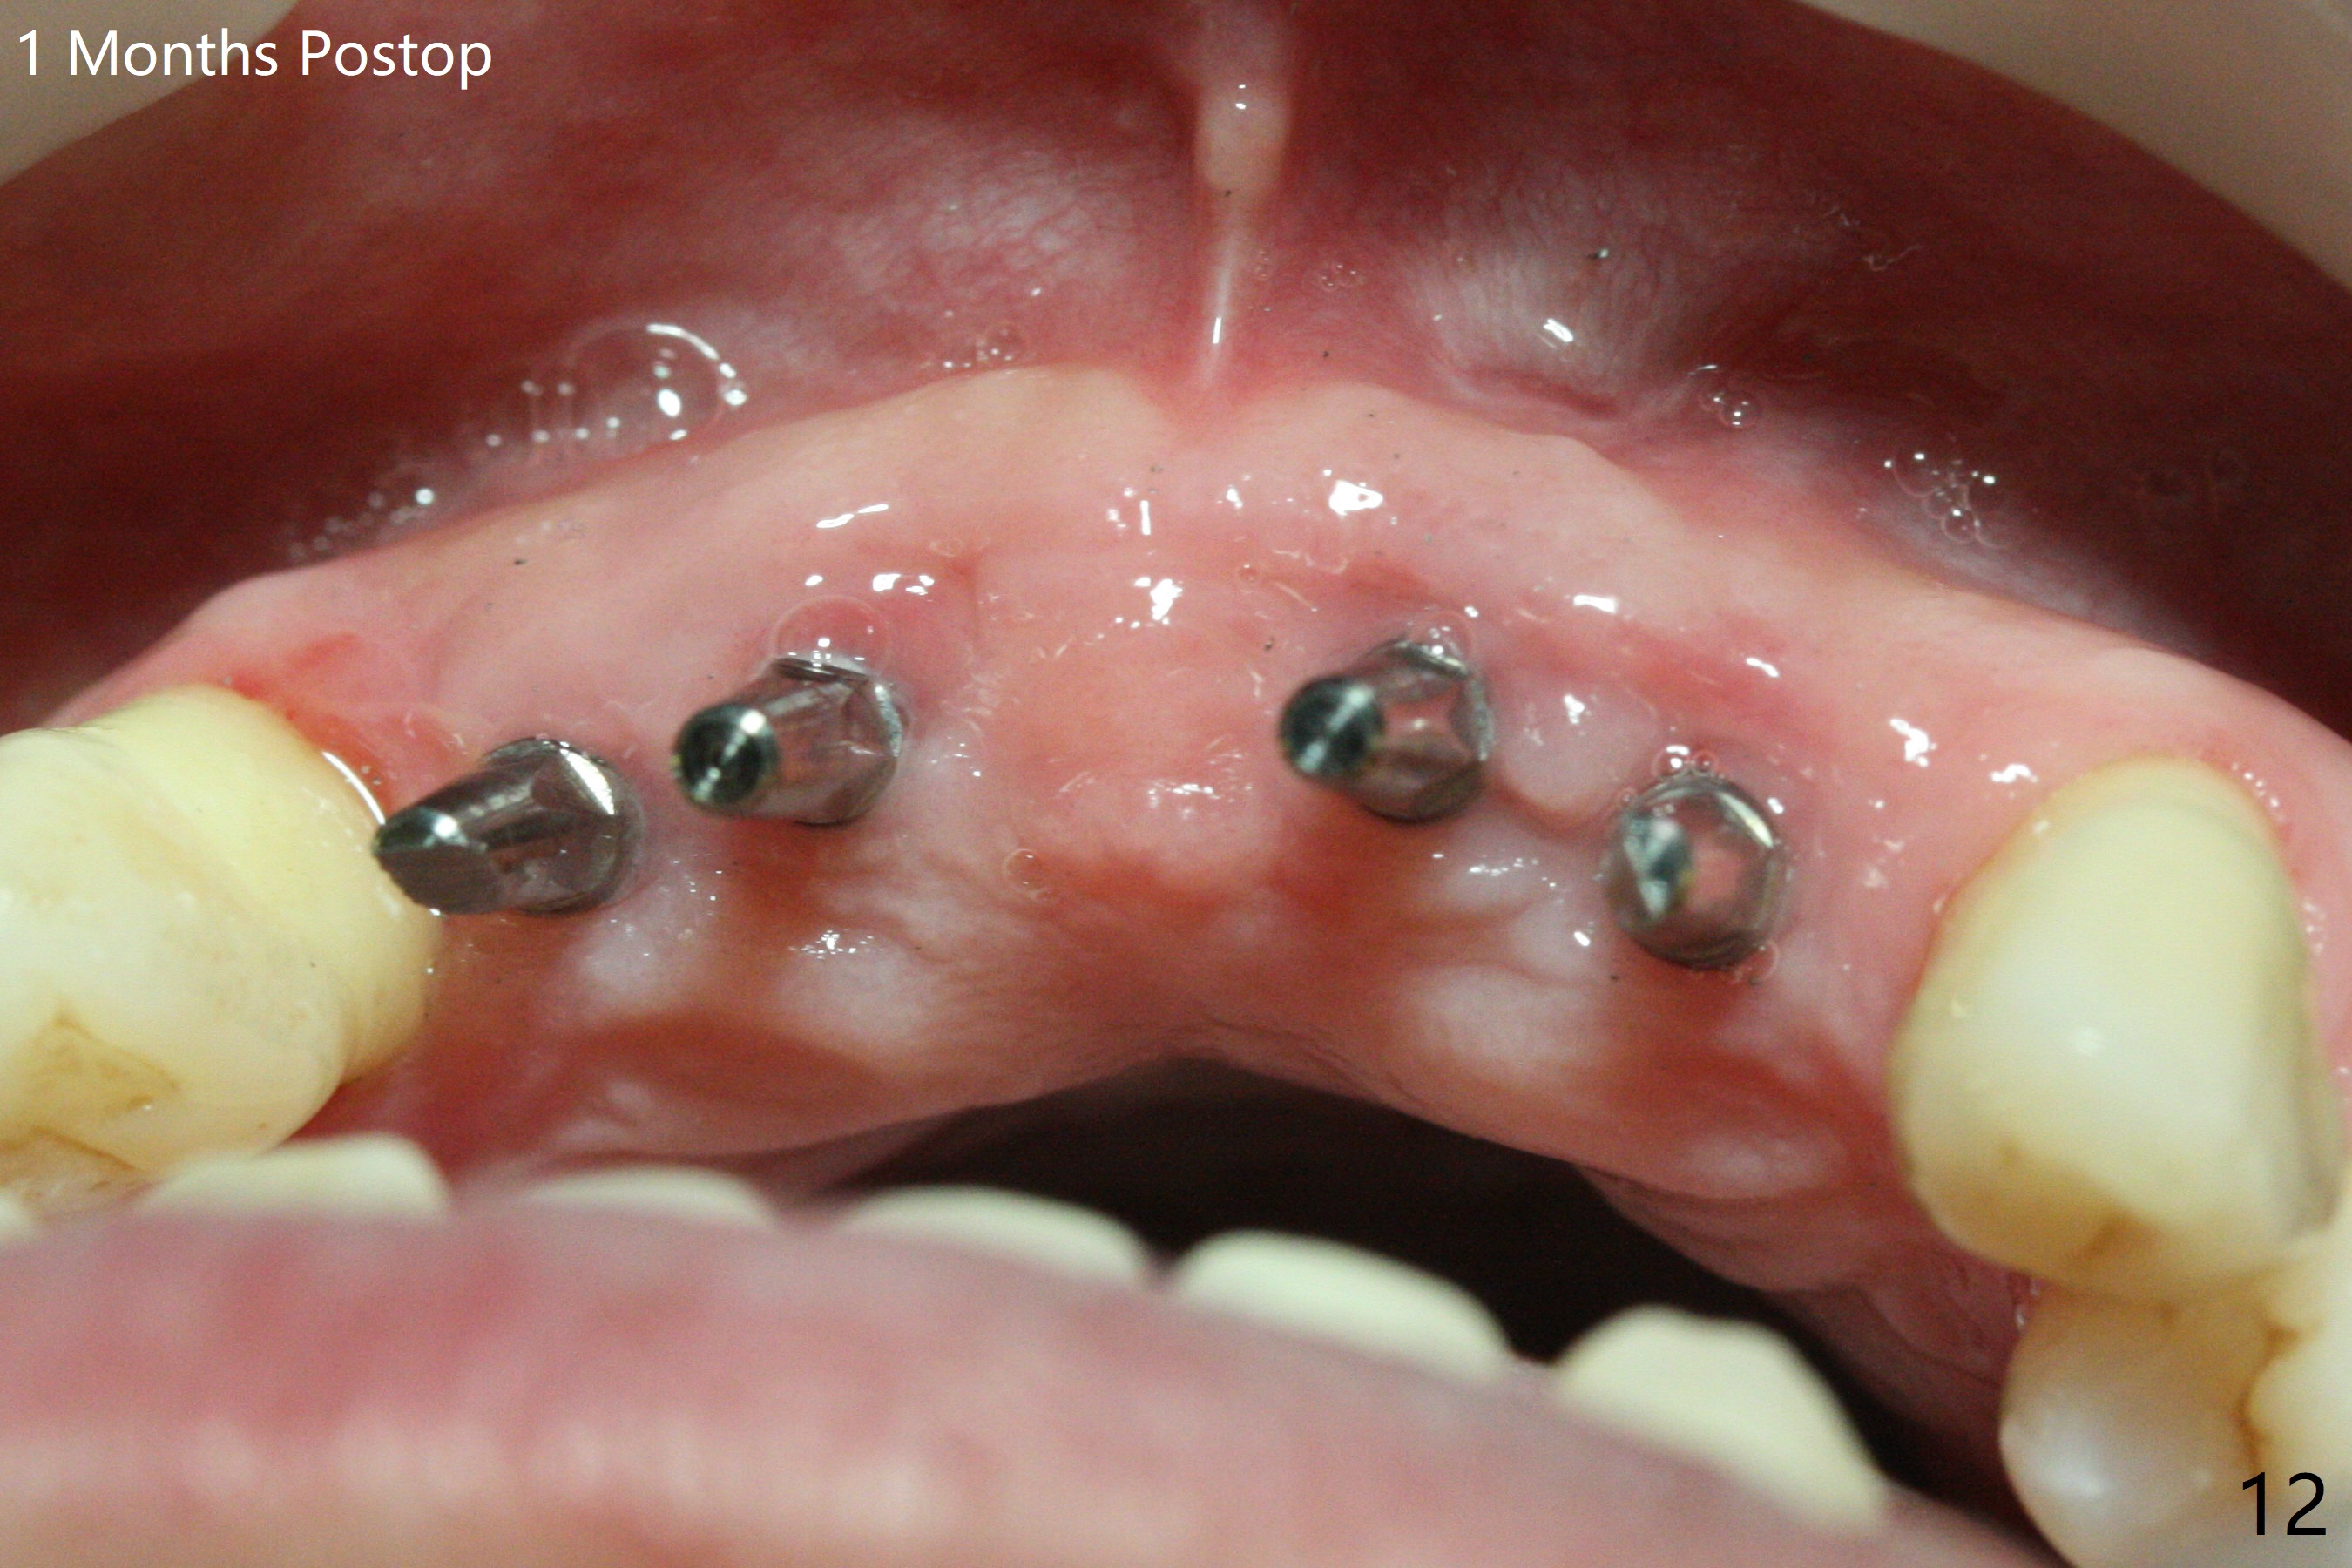

Although the ridge of the maxillary anterior ridge looks moderate in width (Fig.1), the bone is ~4 mm buccopalatally. Suction down surgical stent (Fig.2') made from the lab-fabricated provisional (Fig.2) will be used to check the position and trajectory of osteotomies. PAs taken after initial osteotomies (1.2 mm drill) show those at the central incisors tend to be mesial (close to the Incisive Canal *), while those at the lateral incisor sites distal (Fig.3,4). After adjustment, the position and trajectory of the osteotomies are acceptable (Fig.5,6). To reduce the chance of perforating the Incisive Canal (Fig.3,4 *), 2.5 mm 1-piece implants are inserted with >40 Ncm (Fig.7,8). After deep placement of the implants, Vanilla graft is placed at the crest (Fig.9,10 *). An immediate splinted provisional is fabricated from the suction down stent. The gingiva is healthy around the provisional (Fig.11) and the implants (Fig.12,13) 1 month postop. The provisional is adjusted monthly so that the interdental papillae can be elongated. No bone resorption is observed 6 months postop (Fig.14,15). Crowns are cemented 8 months postop (Fig.16-18). The keratinized gingiva appears to have formed the abutments 8 months postop immediately pre-cementation (Fig.19).